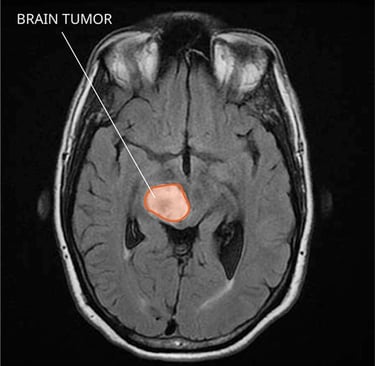

A machine learning model that can detect tumors in MRI brain scans

Can be trained at different medical centers and share the same data

Does not expose patient data, so private information is kept safe